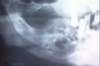

What is this radiographic finding?

Periapical Cysts

►Would need to test both teeth for vitality.

What is this radiographic finding?

Periapical Cyst

What is this radiographic & clinical findings?

Periapical cyst

shows inflammation at site

abscess developed fistula tract thru

soft tissue. Pt will have pain until

pressure is released